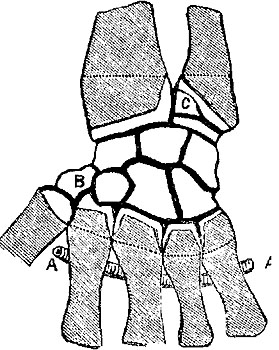

The four plates which precede the letterpress were drawn on wood (from original photographs) by Mr. D.W. Williamson, Melbourne Place, and the lines of incision for the various operations were added by the author.

The rough woodcuts scattered through the work were drawn on wood by the author, and for their roughness he, not his engraver, is responsible. He also hopes that the references in the letterpress will be accepted as sufficient acknowledgment of the true ownership, in those few instances in which the idea of the diagram has been borrowed.